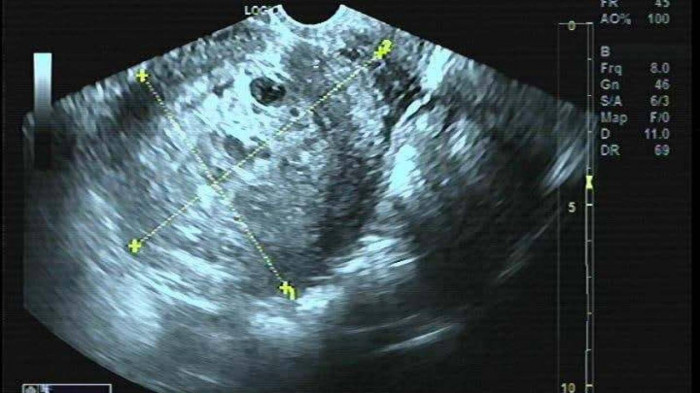

Kết quả siêu âm, xét nghiệm cho thấy bệnh nhân chửa trứng, chỉ định phẫu thuật cắt tử cung

Ngày 3/4, BV ĐK Medlatec thông tin, tại đây đã tiếp nhận nữ bệnh nhân N.K.L, 50 tuổi tới khám do âm đạo ra máu đen và mệt mỏi. Bà L, cho biết, bị chậm kinh 1 tháng nay kèm ra máu đen âm đạo ít một, đau bụng âm ỉ hố chậu phải, người mệt mỏi. Tuy nhiên, vì nghĩ rằng do đang bước vào giai đoạn tiền mãn kinh, bản thân chưa phát hiện bệnh lý bất thường trước đó nên không đi khám. Đến khi thấy hiện tượng ra máu kéo dài, bệnh nhân mới tới bệnh viện.

Tại đây, bệnh nhân được thăm khám và làm các xét nghiệm, và được chẩn đoán chửa trứng và đã phẫu thuật cắt tử cung ngay sau đó. Hiện tại, sức khỏe của bệnh nhân ổn định, cần phải theo dõi chỉ số Beta - hCG định kỳ theo hướng dẫn để phòng biến chứng.